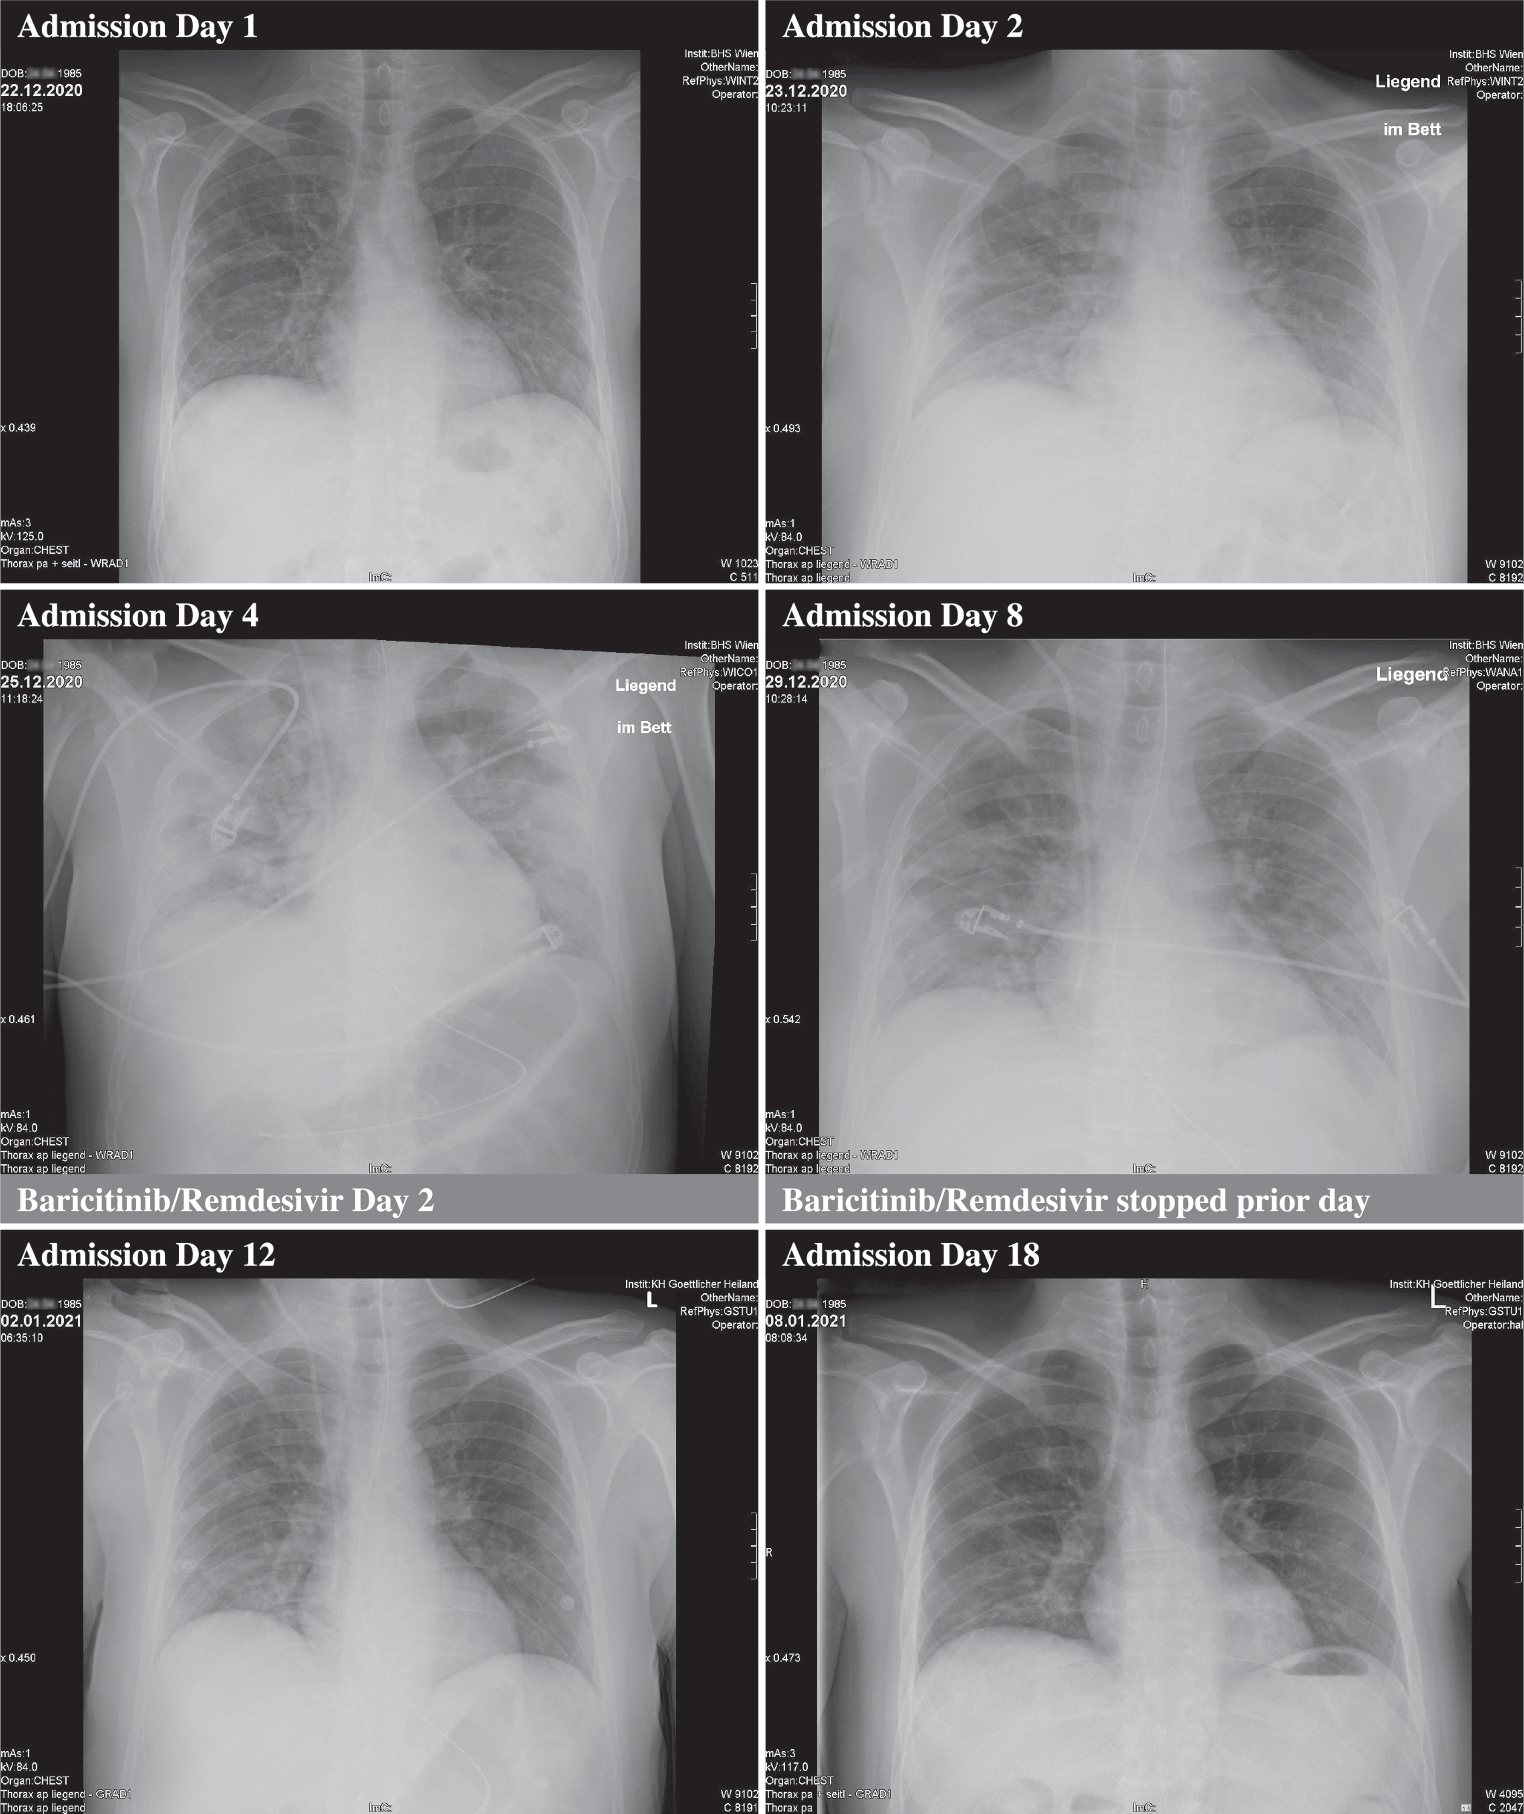

After initiation of the combination treatment with baricitinib and remdesivir in conjunction with dexamethasone, the elevated IL‑6 levels normalized within less than 48 h, the CRP levels were within normal range after 9 days, and consecutive chest X‑rays showed an improvement within 6 days. Inflammatory cytokines remained decreased and within normal range and ferritin remained increased. Bone metabolism showed an isolated increase in osteoclast activity (CTX levels) and the elevated liver enzymes slowly declined (Table 1; Fig. 1).

Fig. 1

Chest X‑ray images at different time points of treatment

We report a case of a young patient with COVID-19-associated, initially mild abdominal symptoms and progressive severe respiratory and neurological symptoms induced by a cytokine storm. Proinflammatory cytokines conspire to elicit from endothelial cells a change from their homeostatic functions to those that can contribute to thrombosis and local tissue injury [1]. In line with WHO recommendations, the standard of care in symptomatic patients includes oxygen supplementation and dexamethasone. The deterioration of clinical symptoms and serological findings demands a therapeutic boost on account of the pathophysiology of this novel disease. Based on recently published data from a double-blind, placebo-controlled trial with a comparable study population, this young and otherwise healthy patient received an additional combination of baricitinib and remdesivir [4]. The administered and recently published combination treatment was safe and immediately lowered elevated levels of IL‑6 and other inflammatory cytokines. It probably reduced the duration at the IMCU with HFNC and led to the patient’s recovery with reduction symptoms of the affected organ systems.

Despite concerns about immunosuppression, secondary infections, or increased risk of thrombosis, the administration of baricitinib in conjunction with dexamethasone or antiviral agents in clinical trials has not been associated with a significantly higher incidence of adverse events. In contrast, the JAK inhibitor baricitinib, with a half-life of 12 h in combination with remdesivir, exerts beneficial effects in terms of the time of oxygen supplementation and the time to recovery. These effects were also observed in this patient and corroborated by numerous serological, radiological and neurological investigations during treatment [47].